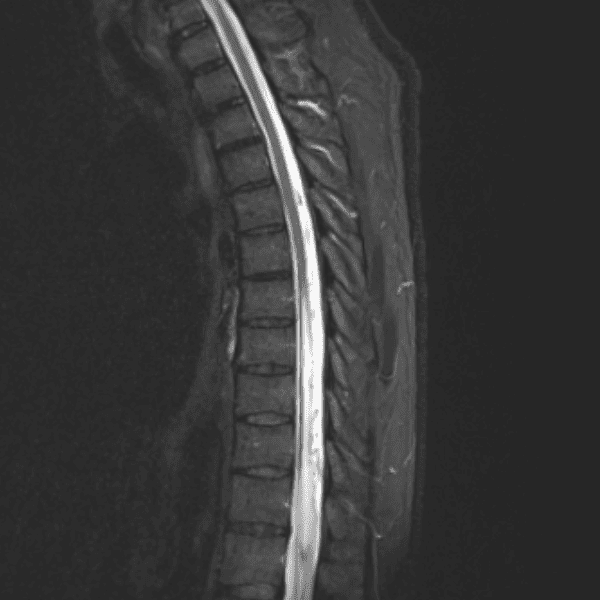

Simulates call by including subtle or difficult cases and some normals.

35 cases